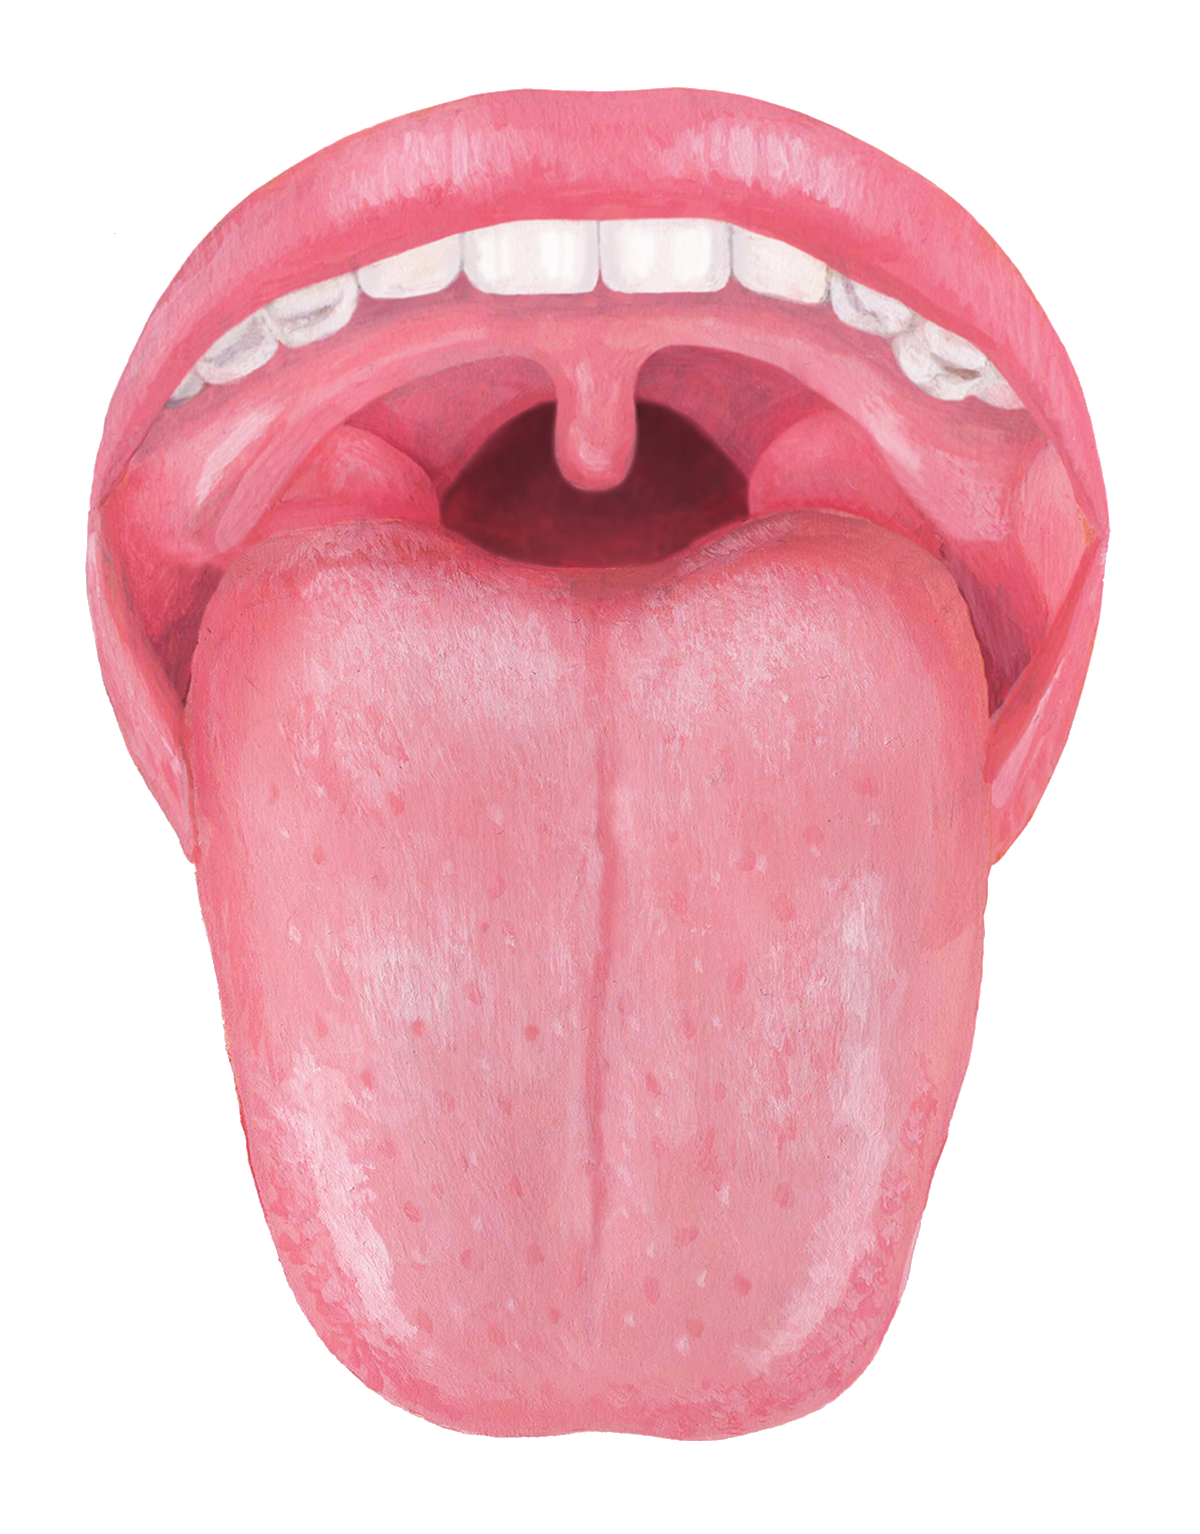

舌がひび割れるのはなぜ?原因や治療法を解説 - 武蔵中原の歯医者なら、中林デンタルケアークリニック武蔵中原駅徒歩5分の歯科医院。

舌がひび割れしてる?考えられる原因や対策について解説します! - 口腔外科DOC。

舌がひび割れしてる?考えられる原因や対策について解説します! - 口腔外科DOC。

舌がひび割れるのはなぜ?原因や治療法を解説 - 武蔵中原の歯医者なら、中林デンタルケアークリニック武蔵中原駅徒歩5分の歯科医院。

舌がひび割れしてる?考えられる原因や対策について解説します! - 口腔外科DOC。

舌のひび割れはなぜ起きる?原因と対処法について徹底解説! – ココシカ。

病気サイン?舌がひび割れる4つの原因。溝状舌・ドライマウスはどう治す?病院は何科?Medicalook メディカルック。

舌のひび割れはなぜ起きる?原因と対処法について徹底解説! – ココシカ。

舌がひび割れるのはなぜ?原因や治療法を解説 - 武蔵中原の歯医者なら、中林デンタルケアークリニック武蔵中原駅徒歩5分の歯科医院。

舌がひび割れるのはなぜ?原因や治療法を解説 - 武蔵中原の歯医者なら、中林デンタルケアークリニック武蔵中原駅徒歩5分の歯科医院。